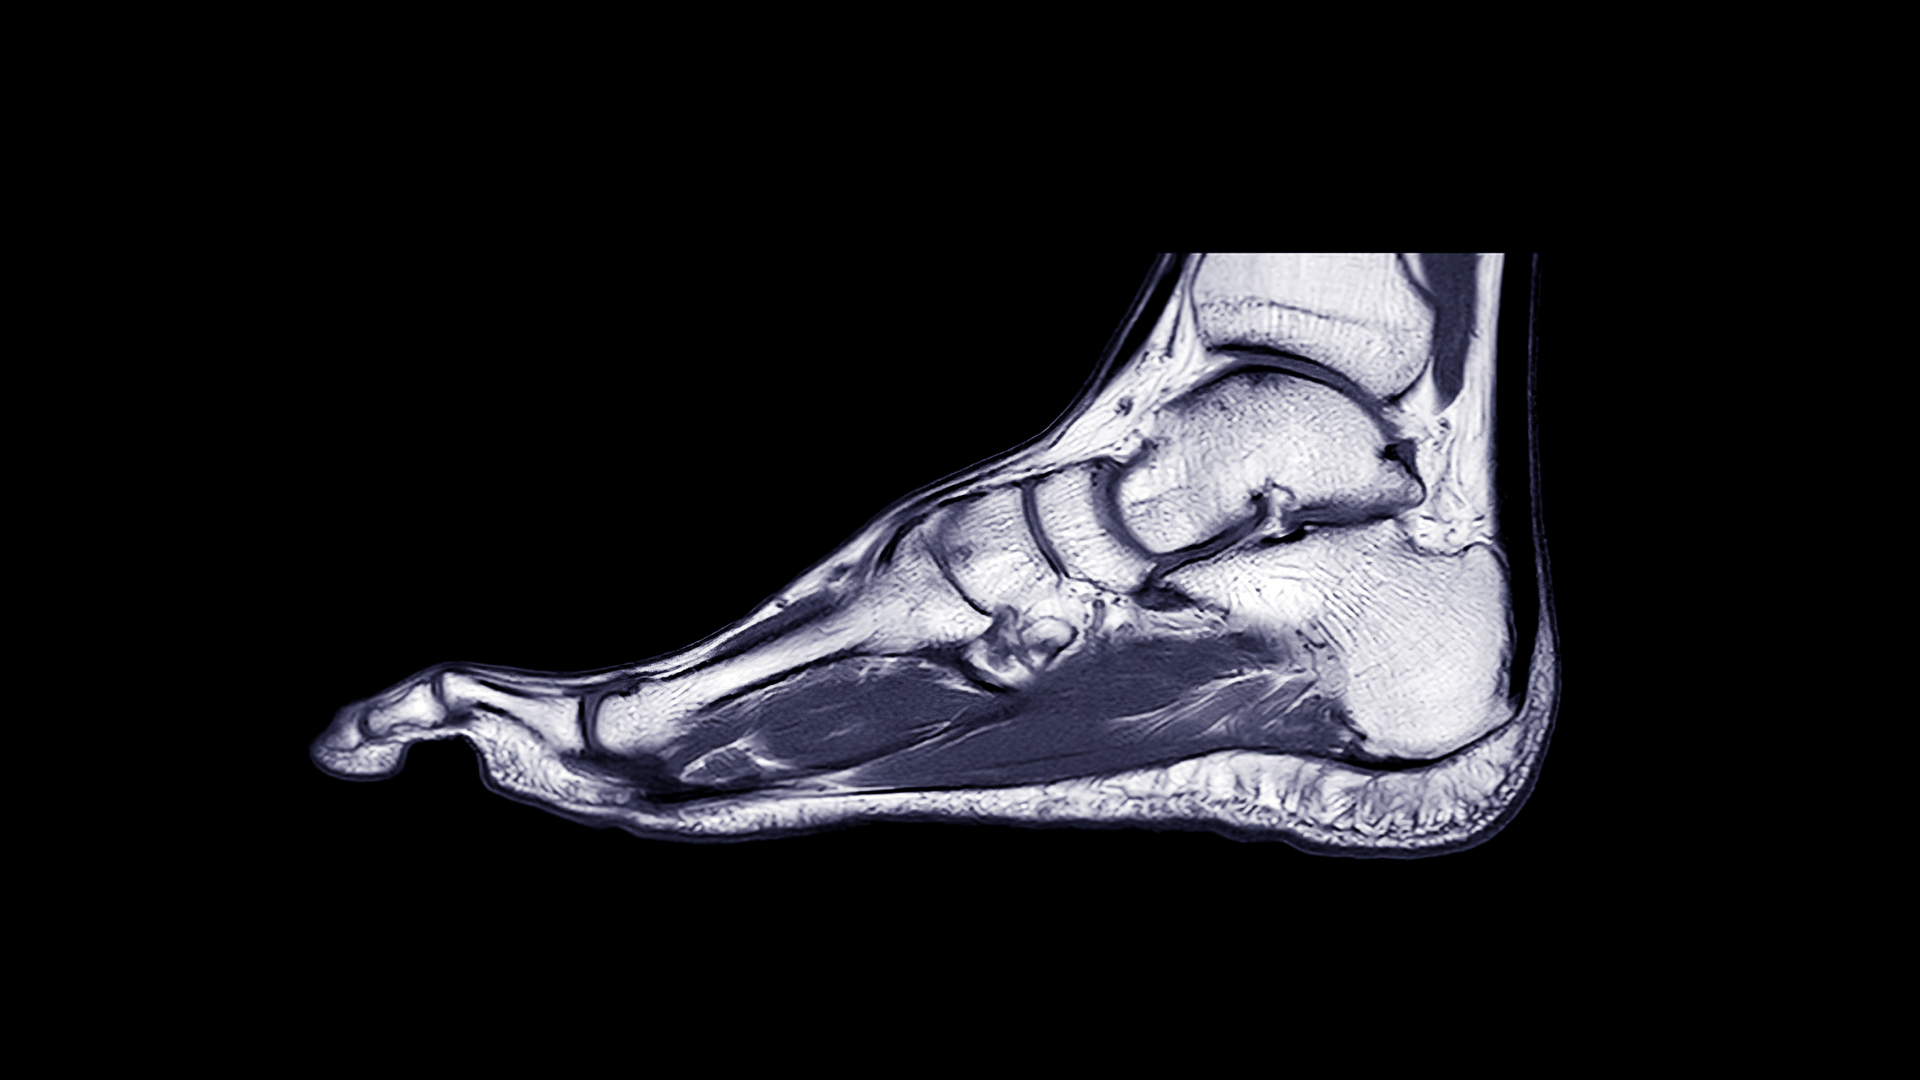

MR Fot är en högupplöst undersökning som visar fotens skelett, leder, senor, muskler, nerver och mjukdelar – helt utan strålning. Den används för att utreda smärta, svullnad, stelhet, gångsvårigheter eller misstänkt skada efter trauma, överbelastning eller långvarigt besvär.

Undersökningen kan påvisa t.ex. stressfrakturer, ligamentskador, seninflammationer, artros, impingement, svullnad i ledkapslar eller nervinklämningar. MR är ofta avgörande när andra undersökningar inte förklarat symtomen.

MR Fot ger detaljerade bilder av ben, senor, leder och mjukdelar i foten och används för att upptäcka t.ex. skador, inflammation eller stressfrakturer – utan strålning.